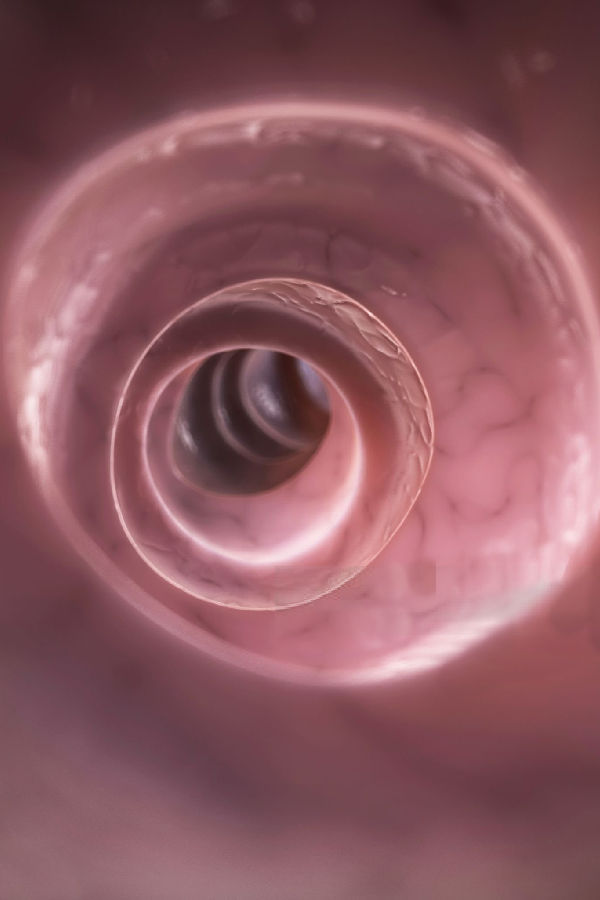

Procedimientos para visualizar el colon, tanto lumen como la mucosa, para tomar biopias o efectuar extirpación de pólipo, dilataciones, detención de un sangramiento y otras.

Diagnóstico precoz a lesiones del tubo digestivo alto y bajo, así como también, procedimientos terapéuticos en caso de hemorragias, obstrucción, volvulación, entre otros.